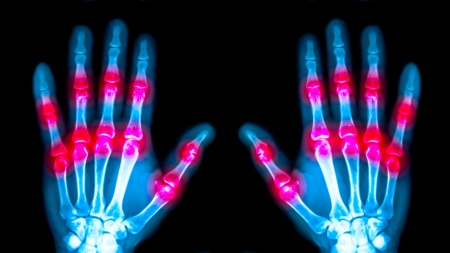

• Inflammatory arthritis